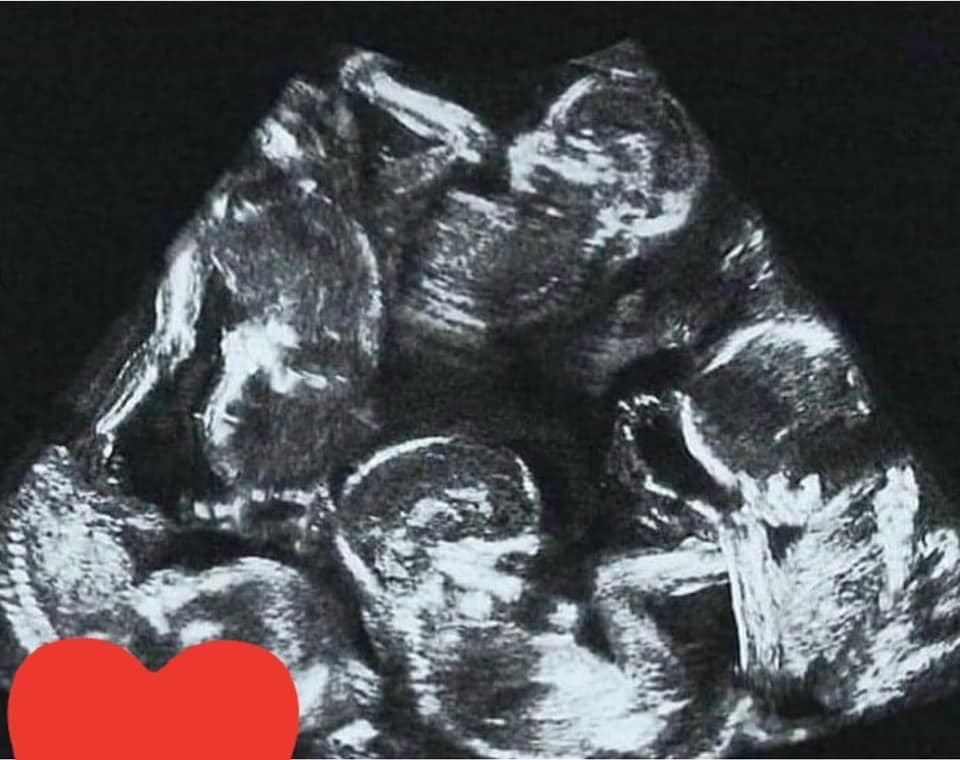

這位媽媽產下 5 胞龍鳳胎 ... 辛苦了!

媽媽辛苦了,光想到每次的餵奶與換尿布加安撫啼哭,5 個一起來,哇!無法想像的累 ...